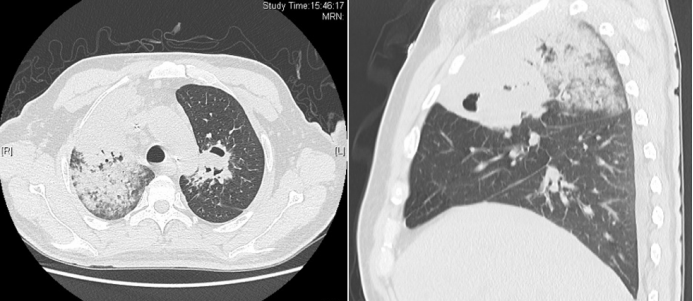

病例1:女性,22岁,既往有1型糖尿病病史,在感染新冠病毒后合并毛霉(米根霉)感染。影像学检查显示双肺存在磨玻璃影,且在此基础上迅速出现实变、空洞及坏死等病变,病情进展极为迅猛(图1)。该患者于2022年底(新冠疫情优化管控后疫情较为严峻时期)从内蒙古前往北京就医,进入急诊室当天便因呼吸衰竭不幸死亡。此病例凸显COVID-19合并毛霉感染的严重性,尤其是对于存在基础疾病(如糖尿病)的患者,病情可快速恶化,致死性极高,也反映出在疫情特殊时期,此类重症感染患者救治面临的严峻挑战。

图片

1  病例1影像学表现